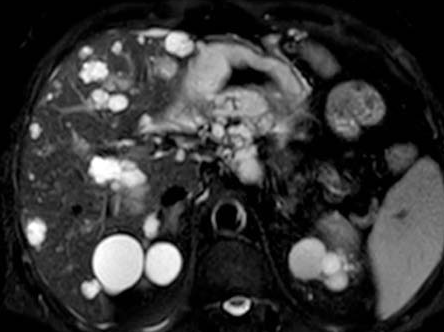

Polycystic liver disease. Red arrow. Infected hepatic cyst (Courtesy Dr. V. Penopoulos)